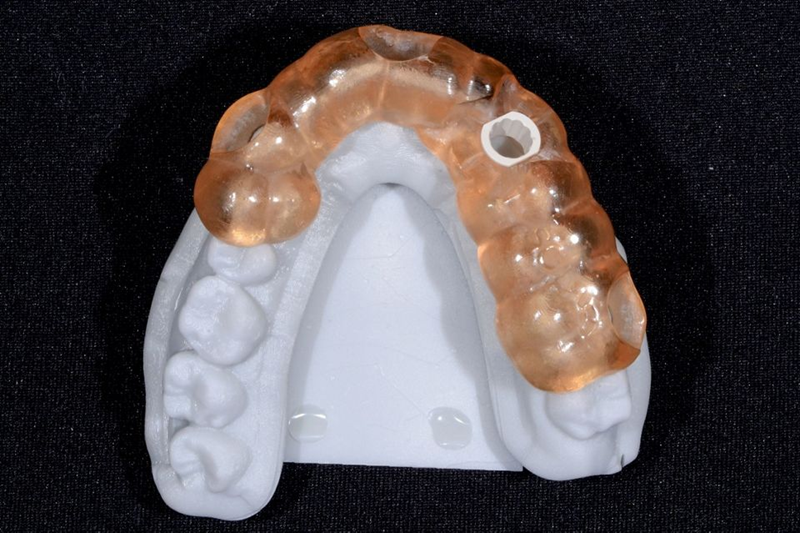

5. 牙科实验室基于数字蜡型(在树脂打印模型上)制作临时牙冠(图 22-24)。

Fig. 22: Lateral view of the printed model: Note that the shape of the provisional canine crown is now in line with the adjacent teeth.

Fig. 23: Provisional crown.

Fig. 24: The occlusal view shows the provisional abutment and...